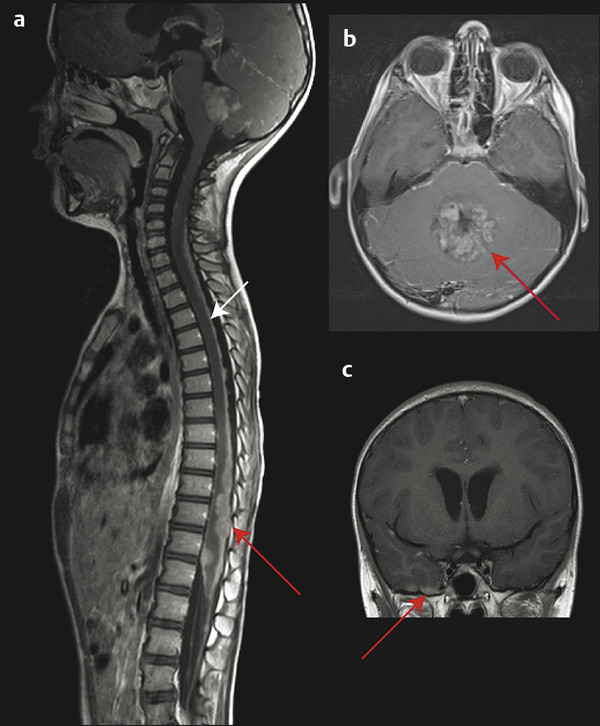

۲. آزمایشهای تصویربرداری: تصویربرداری رزونانس مغناطیسی (MRI) و اسکن توموگرافی کامپیوتری (CT) برای ایجاد تصاویر دقیق از مغز و مکانیابی هرگونه تومور استفاده میشوند.

۴. پونکسیون کمری (Spinal Tap/Lumbar Puncture): نمونهای از مایع مغزی-نخاعی از قسمت پایین کمر گرفته شده و برای وجود سلولهای سرطانی آزمایش میشود. این آزمایش برای تعیین اینکه آیا سرطان گسترش یافته است یا خیر، بسیار مهم است و معمولاً پس از برداشتن تومور یا کنترل فشار در مغز انجام میشود.